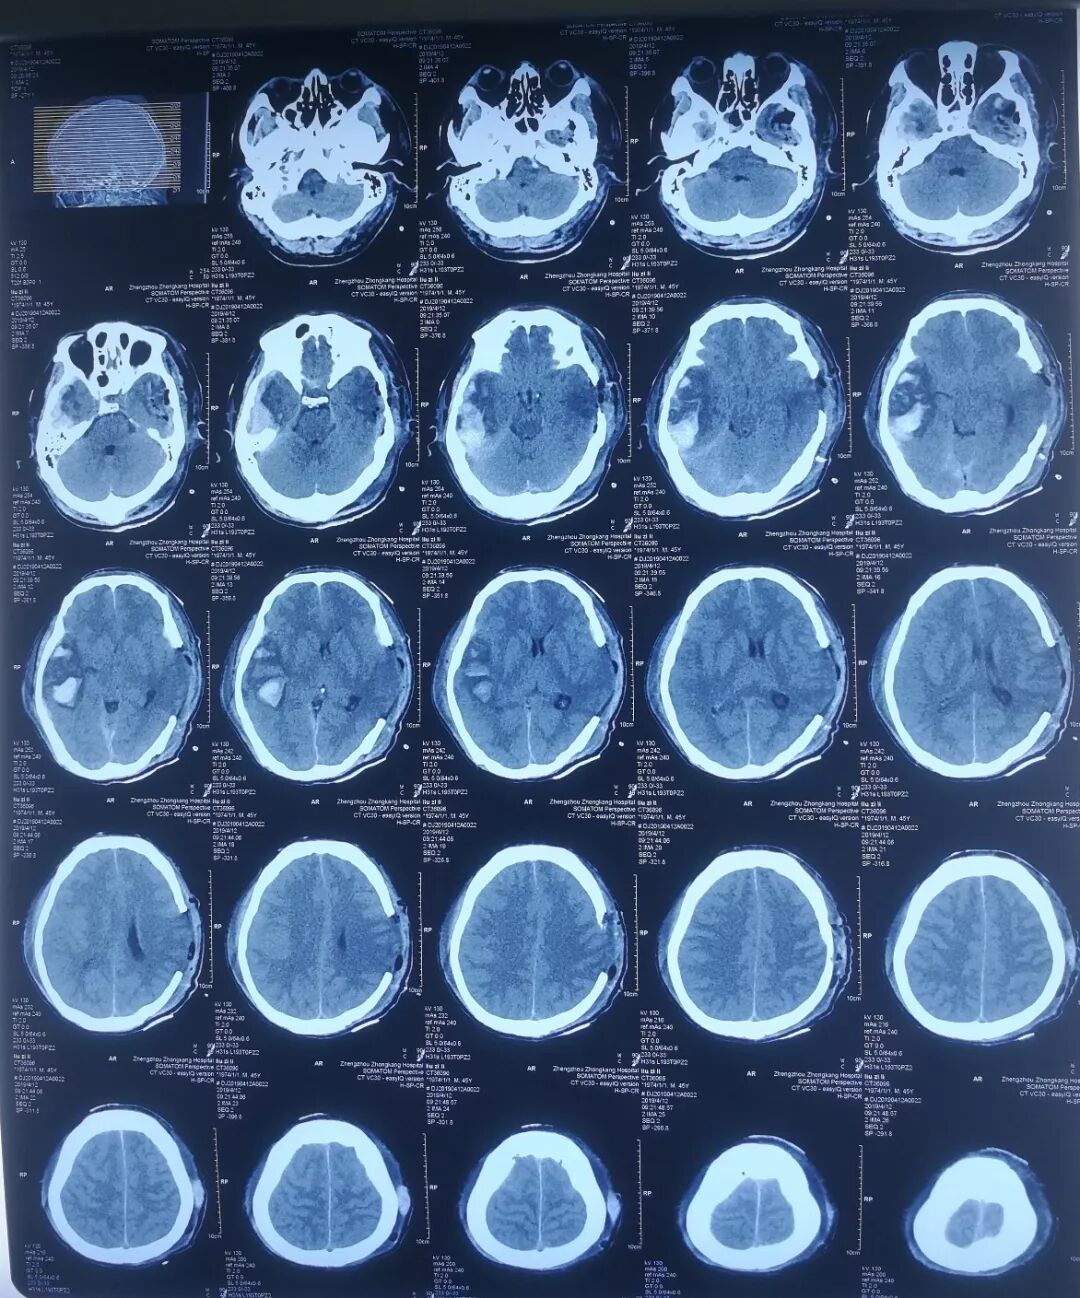

(第一次手术后,刘某CT显示脑挫裂伤加重)

次日复查CT,右侧脑内其中一处脑挫裂伤加重,同侧大脑明显受压,仍需开颅手术。再次与患者家属沟通时,家属没有丝毫犹豫,表示全力配合,眼神里充满了信任。二次术后刘某病情逐渐稳定。